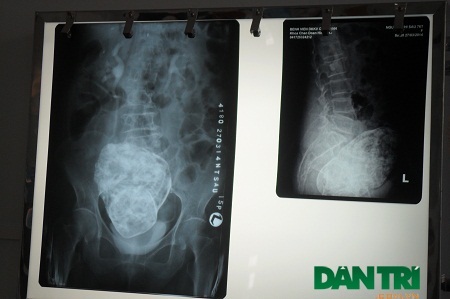

Trước đó, ngày 22/3, sau khi bị đau cột sống thắt lưng và vùng hạ vị, cụ Sáu được con cháu đưa vào Bệnh viện đa khoa Khu vực Cam Ranh để thăm khám. Tại đây, sau khi thăm khám và chụp X-quang, các bác sỹ phát hiện có hình hài bào thai nằm trong ổ bụng của cụ bà.

Kết quả chụp MRI cho thấy có khối bất thường trong ổ bụng vùng hạ vị, ở sau bàng quang, có hình dạng giống thai nhi, khả năng thai vôi hóa.Các bác sỹ nhận định đây là trường hợp thai trong ổ bụng chết lưu đã rất lâu, hóa thạch (lithopedion) và hiện đang có biến chứng gây đau dữ dội vùng hạ vị và thắt lưng, có thể sẽ cần đến phẫu thuật để loại bỏ khối thai này.